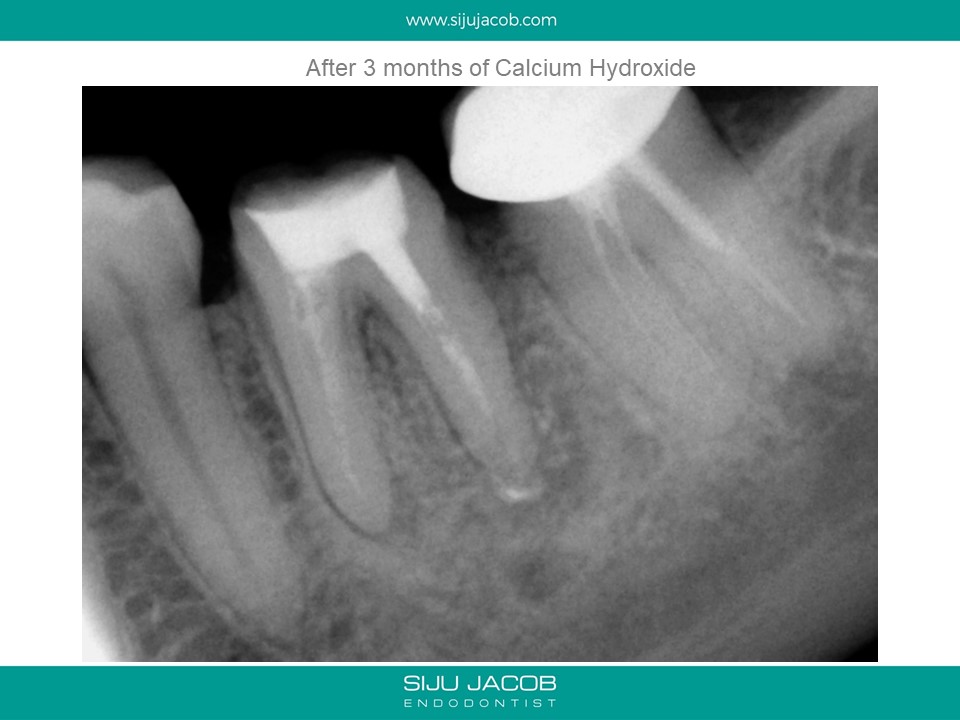

Written by Siju JacobApril 13, 2020 Molar Re-treat with large lesion This patient came with an acute abscess. Disassembly and re-treat with long term Caoh. One year recall shows healing. Share this: Share on X (Opens in new window) X Share on Facebook (Opens in new window) Facebook Like Loading... Related Leave a comment Cancel reply Δ